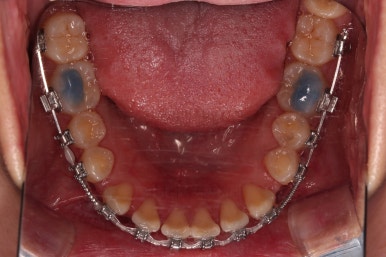

이제 부산치아교정 전후 비교를 해볼게요.

틈새가 예쁘게 모아졌고요.

교합도 좋아졌고, 앞니도 가지런해졌네요.

당연히 얼굴 모습도 마이너스 없이 예쁘게 마무리가 잘 되었습니다.

이상 미니스크류를 이용해 어금니를 전방으로 당겨오면서 틈새를 모아주었던 부산치아교정 치료사례였습니다.